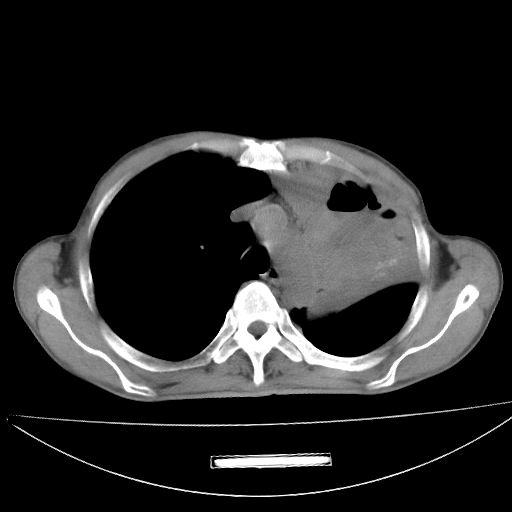

以下是引用杀毒软件在2009-4-28 17:58:00的发言:[br]考虑----左肺慢性肺脓肿形成继发上叶含气不良---抗炎后复查---待排肿瘤所致[br][br][本贴已被 杀毒软件 于 2009-4-28 18:01:26 修改过]